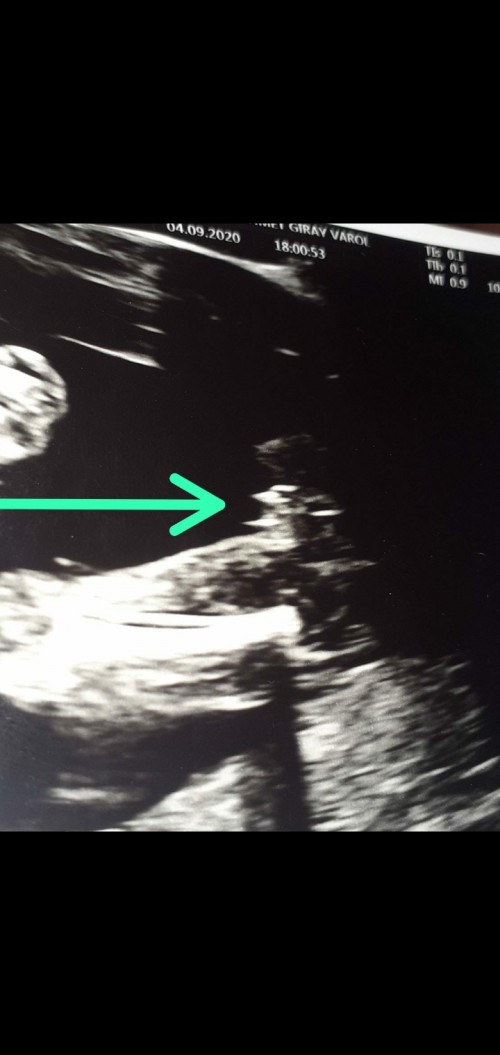

20 Haftada Bebeğin Cinsiyeti Değişir Mi

20 Haftada Bebeğin Cinsiyeti Değişir Mi.

20 hafta hamilelikte neler oluyor